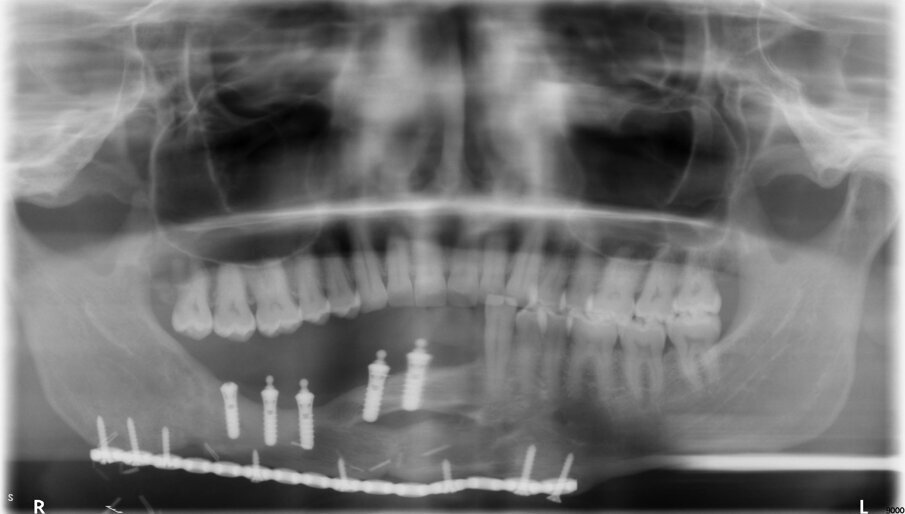

Fig 2: OPG of a patient 9 years following implant supported dental rehabilitation. Stable marginal bone levels are seen.

Denture Guided Epithelial Regeneration is a technique that recreates peri-implant keratinized mucosa in free flap reconstructed jaws. We now have more than a hundred cases with follow-ups of up to 10 years, showing the success of this technique (Figure 1- 3). Moreover, our proteomic studies involving mass spectrometry and immunohistochemical methods have demonstrated that the regenerated mucosa functionally resembles keratinized oral mucosa.